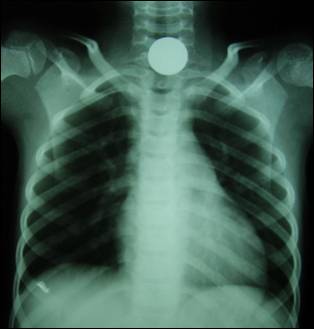

Figure 1: Old

and new coins in comparison – radiologically.

Figure 2:

X-ray neck & chest: Showing opaque shadow of a 5 Rupee coin in the cervical

esophagus in the 1st patient.